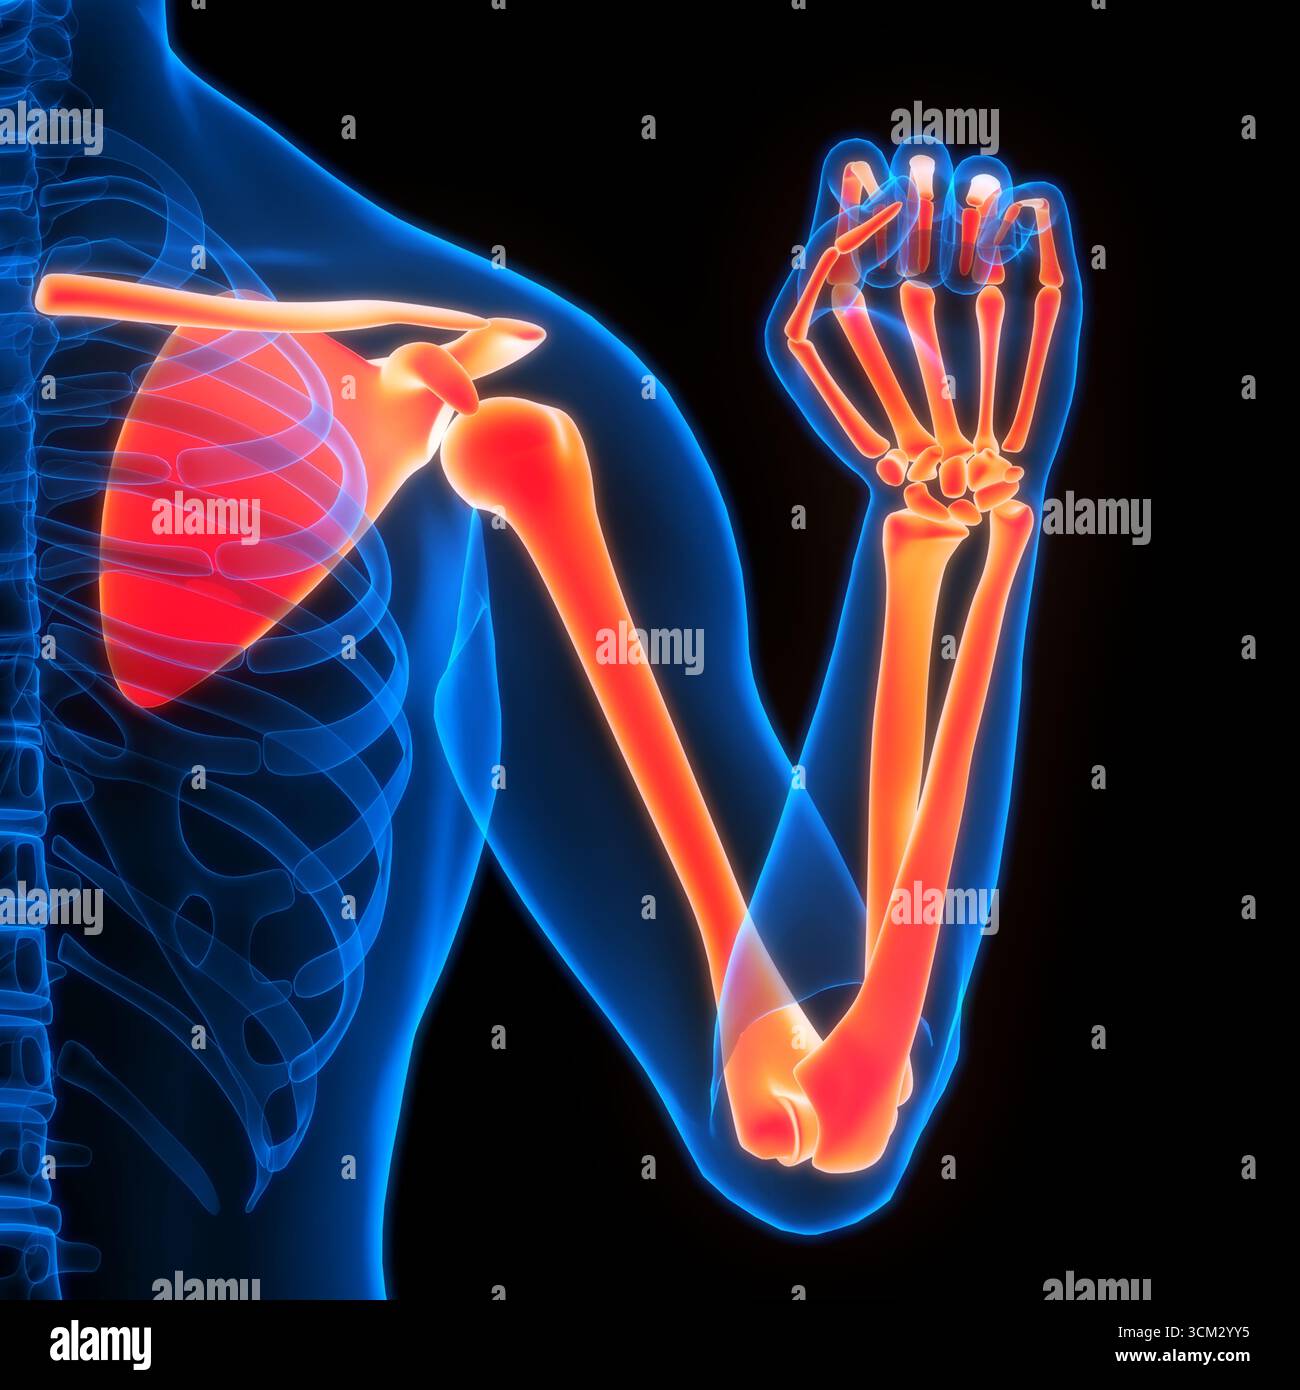

RF3CM2YY5–3D-Illustrationskonzept der Anatomie der Knochengelenke der oberen Extremitäten des menschlichen Skelettsystems

RF2JNYJM7–Präzise Knochen des Arms oder der oberen Extremität des menschlichen Skelettsystems oder Skeletts isoliert auf weißem Hintergrund 3D Rendering Illustration. Anterior und

RF2JNYJM8–Genaue vordere oder vordere Ansicht der Knochen des Arms oder der oberen Extremitäten des menschlichen Skelettsystems isoliert auf weißem Hintergrund 3D Rendering Illustration. Ein

RF3CM31GP–3D-Illustrationskonzept der Anatomie der Knochengelenke der oberen Extremitäten des menschlichen Skelettsystems